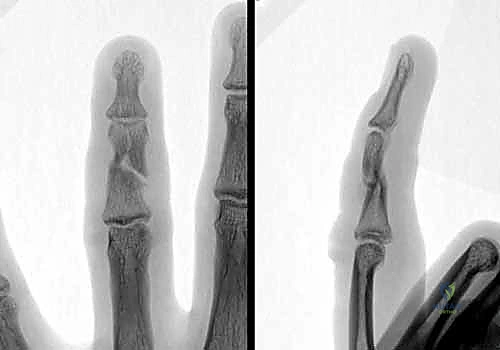

- ظاهرة تداخل الأصابع (Scissoring): وهي من أهم العلامات السريرية التي يبحث عنها د. هطيف. عند محاولة المريض إغلاق يده (صنع قبضة)، يتقاطع الإصبع المكسور فوق أو تحت الإصبع المجاور بدلاً من أن يشير بشكل متوازي نحو العظم الزورقي في المعصم. هذا يدل على وجود تشوه دوراني يجب تصحيحه جراحياً.

- التصوير بالأشعة السينية (X-rays): هو المعيار الذهبي لتشخيص كسور السلاميات. يطلب الدكتور هطيف دائماً ثلاث وضعيات أساسية:

- الأمامية الخلفية (AP View).

- الجانبية الحقيقية (True Lateral View): وهي الأهم لتقييم مقدار الانزياح الزاوي.

- المائلة (Oblique View): تساعد في رؤية الكسور الشعرية الدقيقة أو الكسور المفصلية الخفية.